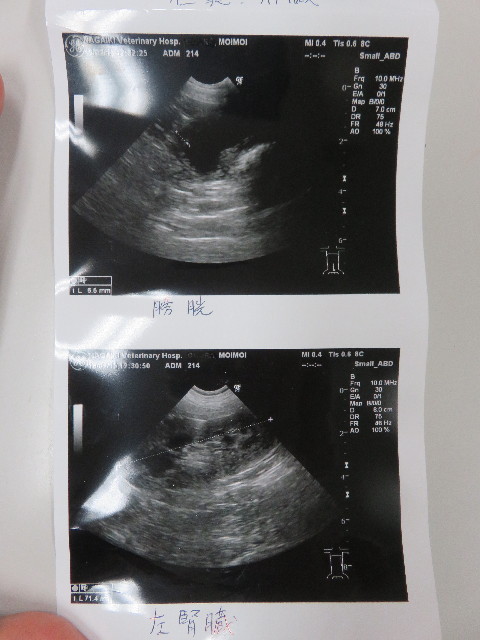

●エコー

○脾臓のマス、20.7×11.9cmと前回(前回12.7は17.5×12.2)

よりけっこう大きくなってしまっていました。

(前回はその前より小さくなっていた)

先生的には悪いものにはみえないので、これで脾臓をとる必要

があるとは思えない。とのこと。